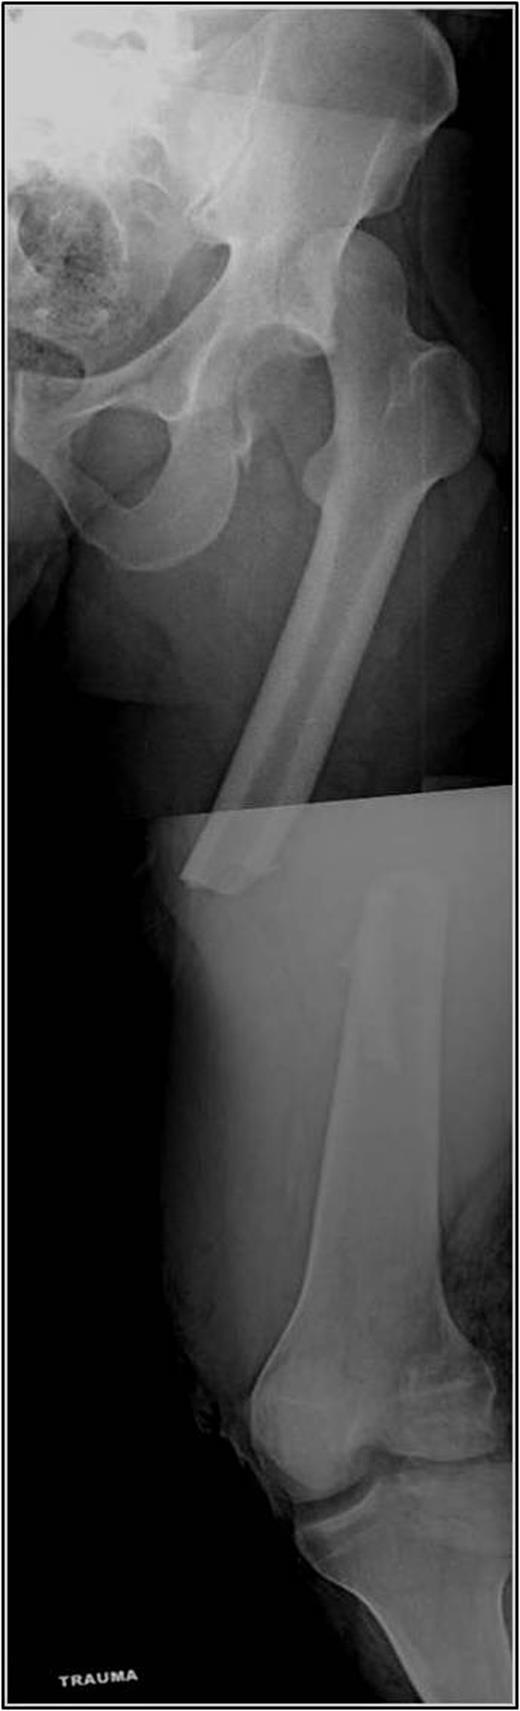

A 35-year-old male was involved in a high-speed urban dirt biking accident. The patient was stable with a GCS of 15 and was neurovascularly intact. His left knee exhibited a 10 × 20 cm medial traumatic arthrotomy and his thigh compartments were soft and compressible. Imaging revealed a left hip postero-superior dislocation, posterior wall acetabular fracture, ipsilateral transverse femoral diaphyseal fracture and an engaging hill-sachs-type lesion of the femoral head with the postero-superior acetabulum (Figs 1–3). Cefazolin, gentamicin and tetanus prophylaxis were administered along with a bedside washout of the traumatic arthrotomy. The patient was medically cleared for operative intervention as all blood work and further imaging were normal.

Coronal and axial CT pelvis of the left femoral head engaging with the postero-superior acetabulum.